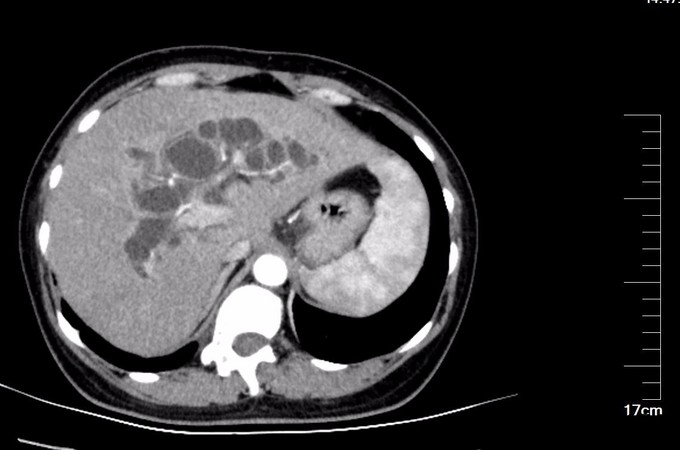

查体:腹部略膨隆,未见胃肠型及蠕动波,未见腹壁曲张静脉,右上腹部压痛阳性,无反跳痛或肌紧张,未及包块,肝脾肋下未及,Murphy氏征阳性,肝区扣痛阳性,肾区无扣痛,肠鸣音减弱,约4次/分,未闻及气过水声。 辅查: MR平扫+增强:肝脏大小形态未见异常,各叶比例正常,未见异常信号灶。肝内胆管、胆囊管及胆总管多发囊状扩张,胆总管直径6cm左右,壁厚且明显强化,腔内点状T2WI低信号影。胆囊饱满,其内可见聚集点状低信号影,胆囊壁增厚且明显强化。门脉血管显示清楚,走行正常。胰腺形态信号未见异常,胰管未见扩张。脾脏不大。增强扫描未见异常强化病灶。 MRCP:胆囊体积增大,肝内胆管、胆囊管及胆总管多发囊状扩张。胰管显影,形态走行未见异常。 CT 胆总管囊状扩张,囊壁较厚,前壁见点状钙化,较宽处直径约6.7cm,胆总管末端壁增厚,管腔狭窄;增强扫描扩张胆总管壁明显强化。肝内胆管扩张,胆囊增大,胆囊壁增厚、强化尚均匀,囊内未见异常密度影。 肝内未见异常密度影。胰腺形态、密度未见异常。脾不大。腹膜后未见确切肿大淋巴结影。

诊断: 胆总管囊肿 治疗:全麻下手术治疗。术中探查,见胆囊大10x6x4cm,肝门部可触及肿大胆总管,直径约6cm,向下延续到胰腺段,切除胆囊,于肝总管横断,向下剥离胆总管,直至胰腺段,仔细分离胆总管与胰腺,避免胰腺组织破碎,直到胆总管变细部位,切断之,远端缝扎,继续行肝管空肠Roux-en-Y吻合术。术后病理胆总管绒毛管状腺瘤,伴高级别上皮内瘤变,有恶变趋势,慢性胆囊炎。

术后检测引流液淀粉酶,术后第一天引流液淀粉酶583U/L, 按照血淀粉酶正常值3倍定义胰瘘,存在胰瘘,术后第4日272 U/L,术后7日118 U/L,已经正常。复查腹部CT, 上腹壁见手术瘢痕影,腹壁下见少量渗出、积气;肝内胆管仍扩张、程度较前减轻,胆囊未见显示,胆囊窝留置导管、局部积气。胆总管囊肿病因不清,对此假说繁多,大多数病例被认为是先天性发育不良所致。胆管壁薄弱有认为管壁的支撑组织存在先天性缺损或存在异位胰腺组织使管壁处于低张状态;胆总管远端梗阻,致管内压力增加从而引起扩张。 分为三型:普通型,憩室型,十二指肠内胆总管膨出,本病例属于普通型。临床表现为间歇性上腹痛、右上腹肿块和黄疸,称为胆总管囊肿三联征,本病例无黄疸。一旦作出诊断,即应采取手术治疗,内引流为宜。胆总管囊肿不手术,会继发结石,并且恶变,本病例经过病理证实已经出现恶变倾向,早期尽快明确诊断,及时手术治疗是此病预防的关键。